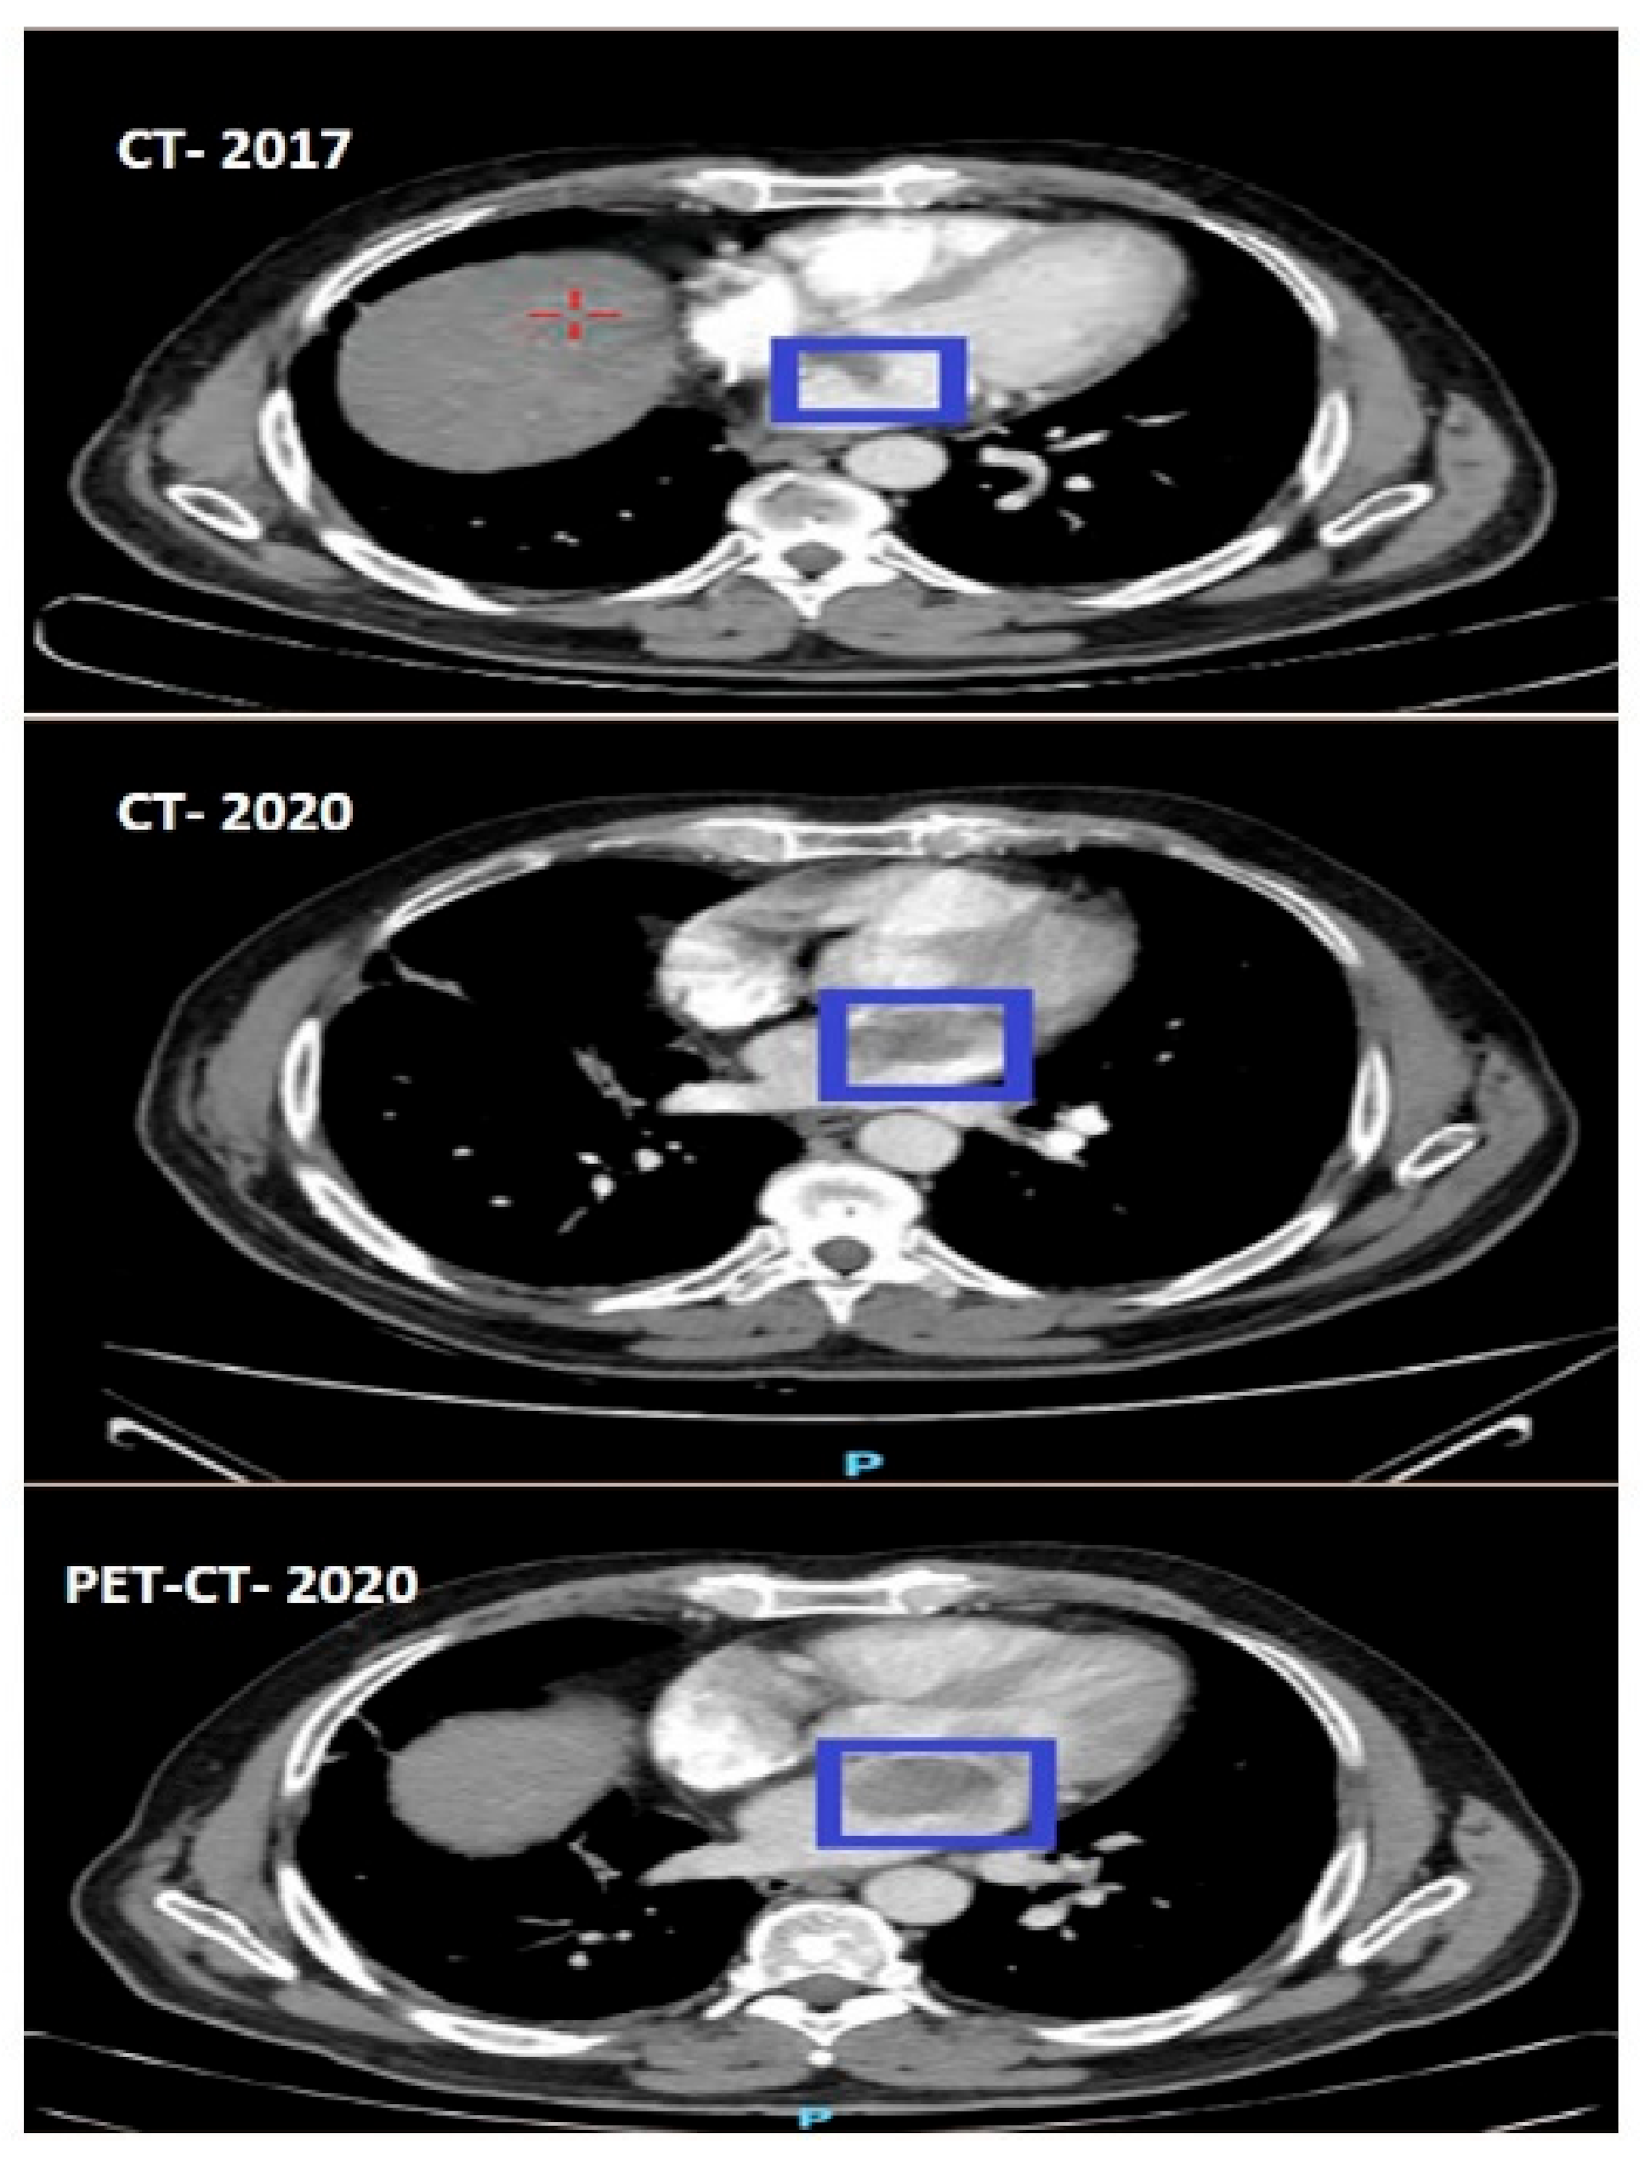

In February 2020, during a follow-up, a chest CT scan revealed a suspicious lymph node in the left side of the mediastinum, measuring approximately 2 cm in diameter, as well as a mass in the left atrium. A month later, a total body PET-CT scan was performed, which showed slight hypermetabolic activity in the suspicious lymph node, diffuse pulmonary nodules with the largest diameter up to 5 mm, and a mass in the left atrium. A multidisciplinary conference involving specialists from various fields concluded that the atrial mass was likely a myxoma. Excision of the mass was recommended instead of observation. Upon reviewing previous CT and PET-CT scans (Figure 2), it was observed that the mass could be seen on the CT scan from December 2017 and had increased in size on subsequent scans. The cardiac mass was situated within the previously radiated mediastinal field. Other abnormalities detected were not indicative of recurrent disease. Close monitoring was advised to detect any potential recurrences or additional primary tumors.

Figure 2.

The progressive growth of the myxoma (blue squares) from 2017 until its subsequent removal.